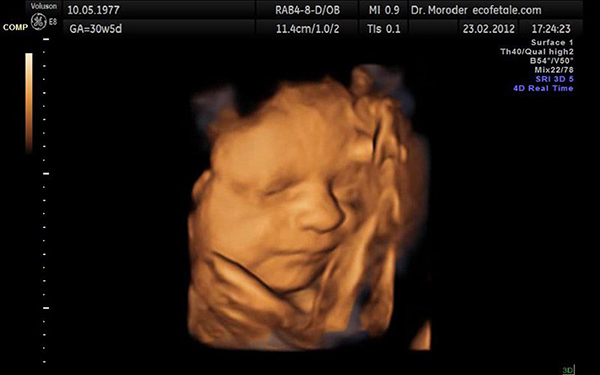

Thời điểm mà bạn nên thực hiện siêu âm 4D lần thứ 2 đó là vào khoảng tuần thứ 21 đến 24 của thai kỳ. Lúc này, bé sẽ được đo các chỉ số để biết em bé có đang phát triển bình thường hay không.

Khi siêu âm 4D lần 2, bác sĩ còn có thể xác định một số những dị tật như: hở hàm ếch, các bệnh lý liên quan đến nội tạng như tim, phổi, thận,…

Sau đây sẽ là một số chỉ số thai 21 tuần siêu âm 4D mà bạn sẽ thấy khi đi siêu âm:

– Chỉ số BPD: đây là đường kính lưỡng đỉnh. Chỉ số này nếu nằm trong khoảng từ 44 đến 56 thì là tốt

– Chỉ số FL: đây là chỉ số đo độ dài xương đùi. Thai 21 tuần siêu âm 4D sẽ được coi là phát triển bình thường nếu chỉ số FL nằm trong khoảng từ 32-38.

– Chỉ số AC: chỉ số này sẽ cho biết chu vi vòng bụng. Lúc này, vòng bụng của bé sẽ nằm trong khoảng từ 147 đến 187.

– Chỉ số EFW: khi thai 21 tuần siêu âm 4D, bạn sẽ thấy cân nặng của bé có mức trung bình nằm trong khoảng từ 331-467.

– Chỉ số HC: là chỉ số biểu thị chu vi vòng đầu. Ở tuần 21, chu vi vòng đầu của bé sẽ nằm trong khoảng từ 170-200.